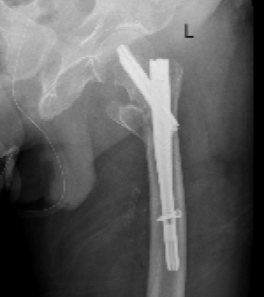

ICU与呼吸内科团队确保患者拔管后呼吸功能稳定;心血管内科、内分泌科精准调控血压、血糖至精准范围;神经内科评估脑梗后状态。手术麻醉科量身定制创伤最小、最稳定的个性化麻醉与监测方案,严阵以待可能出现的循环呼吸波动。在此基础上,骨科团队最终决定采用微创的“闭合复位髓内钉内固定术”,力求以最短时间、最小创伤完成固定。

在万全准备下,手术如期展开。术中,多学科团队配合默契,操作精准流畅。仅用时40分钟便成功完成骨折复位与固定,术中出血极少,患者生命体征平稳。这场高风险手术取得了关键性胜利。